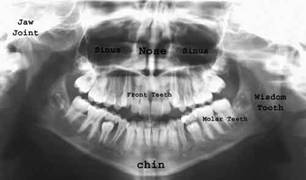

Anatomie radiologica OPT